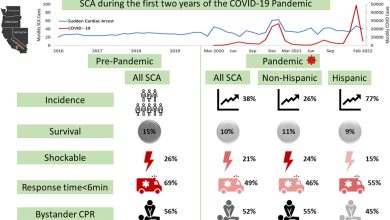

Risco de parada cardíaca súbita aumenta acentuadamente no condado de Ventura

Resumo gráfico. Crédito: Ritmo do coração (2023). DOI: 10.1016/j.hrthm.2023.03.025 Em um estudo entre residentes do Condado de Ventura, Califórnia, as…